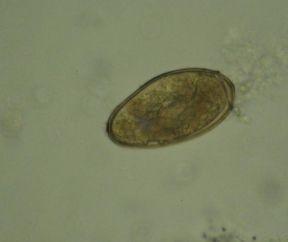

วัดความรู้ว่ารู้จักไข่พยาธิแค่ไหน